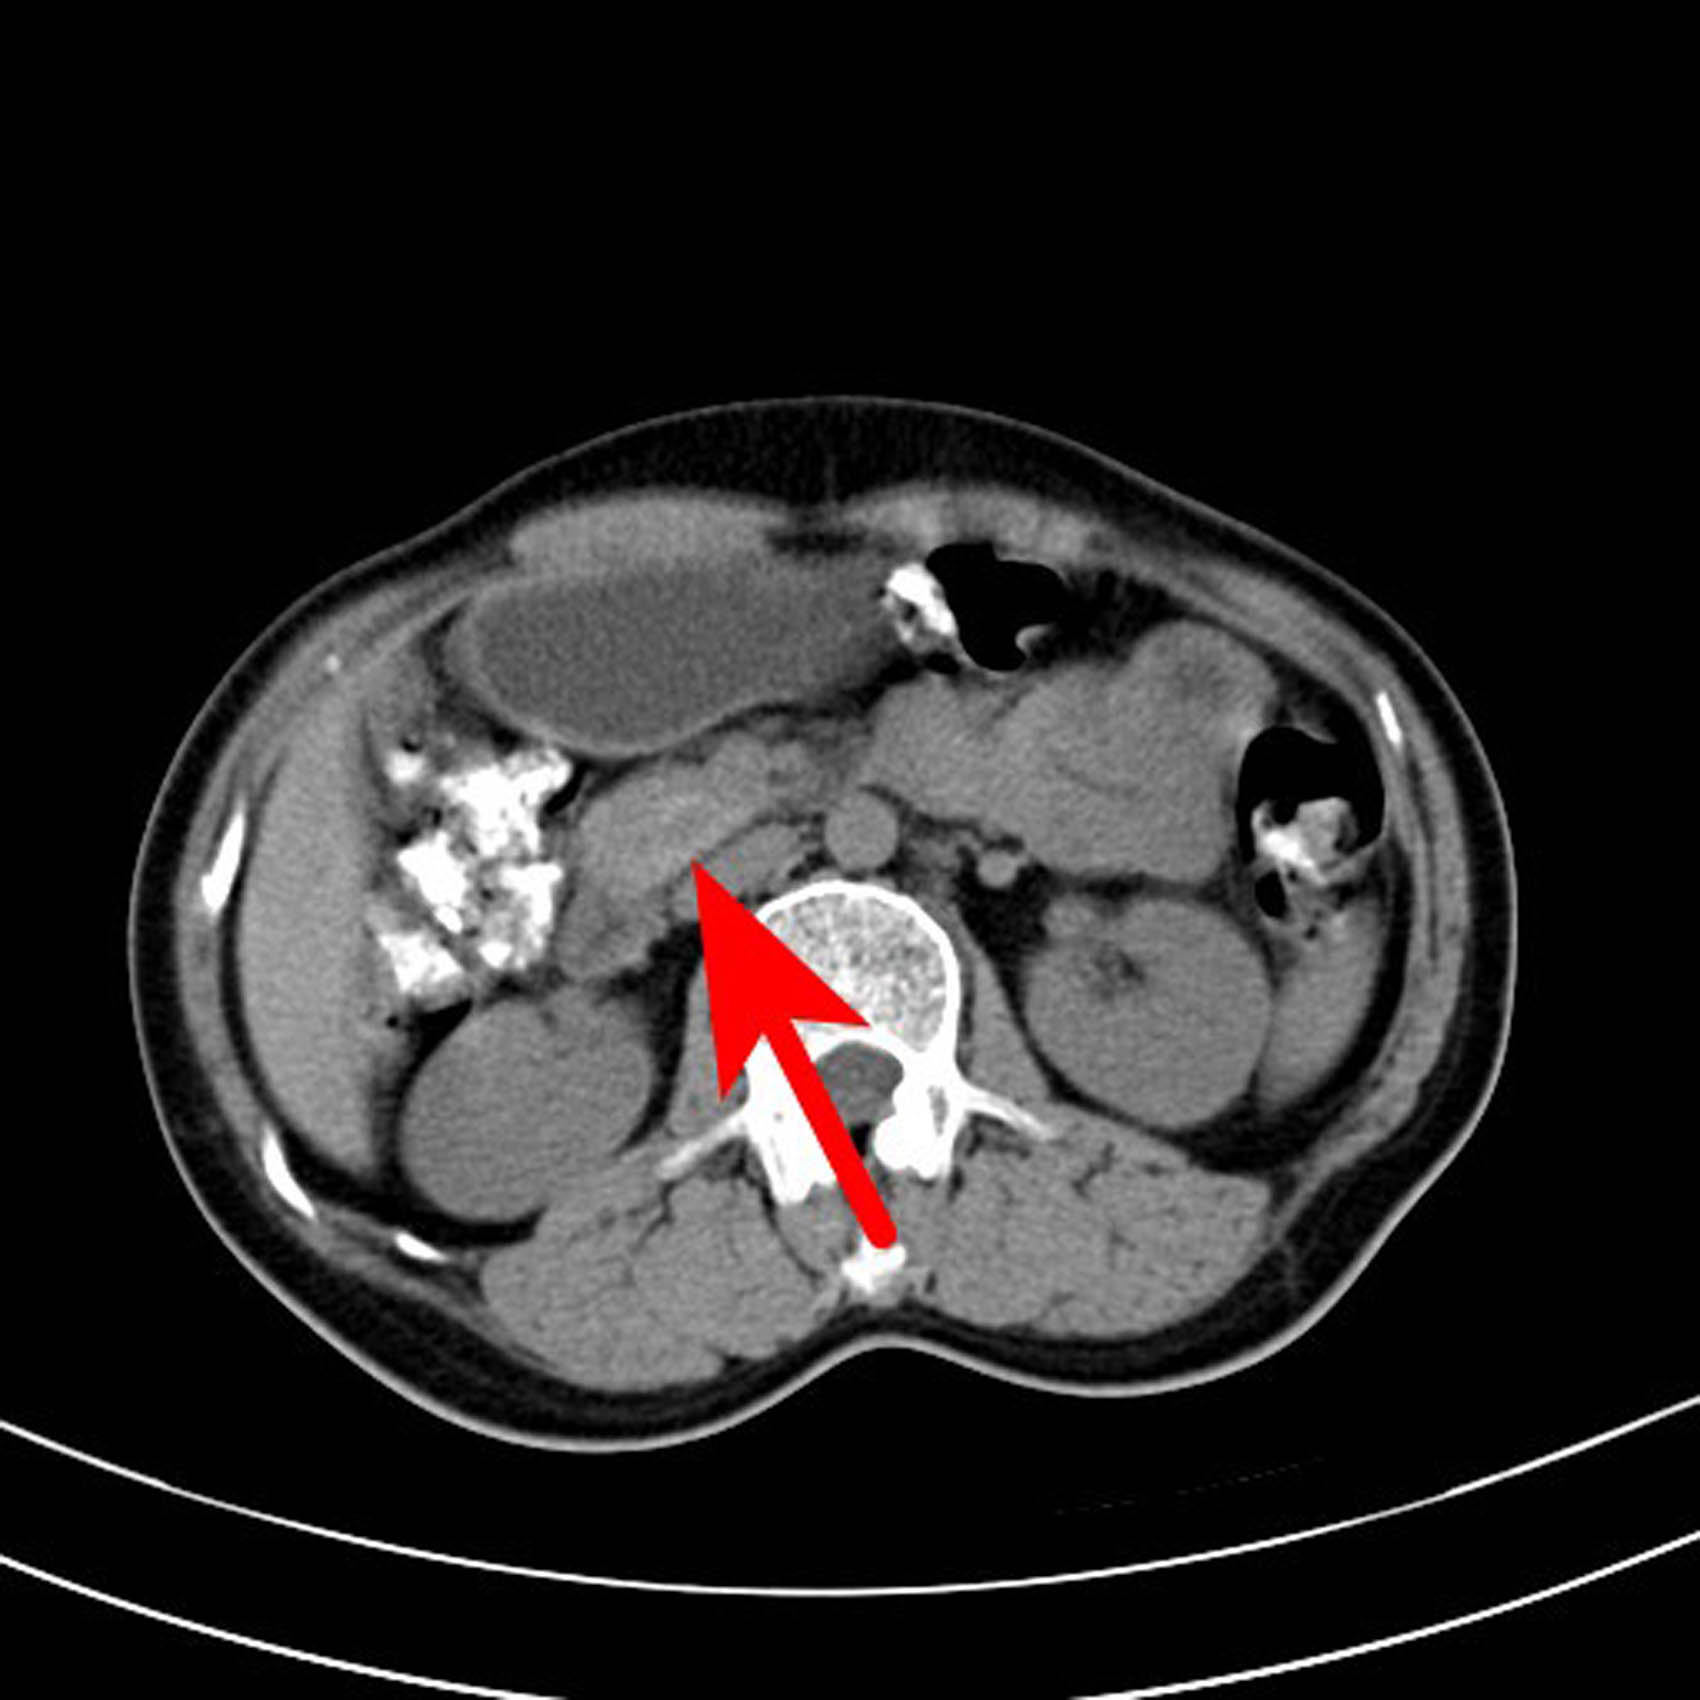

The following imaging tests were conducted. Specifically, the enhanced computed tomography (CT) of the entire abdomen revealed a slightly dense nodular shadow in the head of the pancreas with a maximum transverse diameter of approximately 19 mm, clear borders, and a small cystic hypodense shadow and punctate calcification shadow within, as well as an obviously unevenly enhanced lesion and no enhancement of the hypointense shadow. The CT value was approximately 58 HU on the conventional scan, 192 HU during the arterial phase, and 174 HU during the portal venous phase, and the hypodense shadow was not enhanced. A neuroendocrine tumor was considered (Figures 1–6).

CT scan of the abdomen of the patient. The arrow points to a nodular slightly high-density shadow on the head of the pancreas, with a maximum transverse diameter of about 19 mm and a clear boundary, and a small saccular low-density shadow and a punctate calcification shadow.